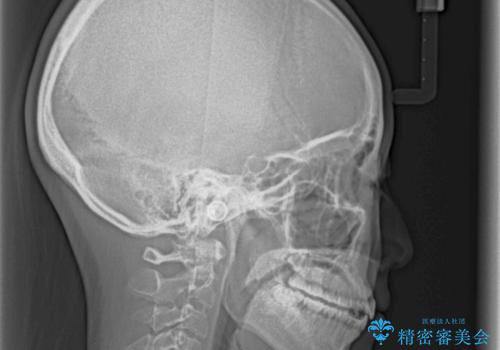

- 前歯の捻れと、ちょっとした出っ張りを気にして来院された患者様です。

歯と歯の間を削る(IPR)ことでデコボコを解消し、インビザラインで整えることとしました。

インビザライン治療特有の奥歯が接触しない時期が続き、当初予定よりも期間がかかりましたが、最終的には安定した咬み合わせと、整った前歯になりました。